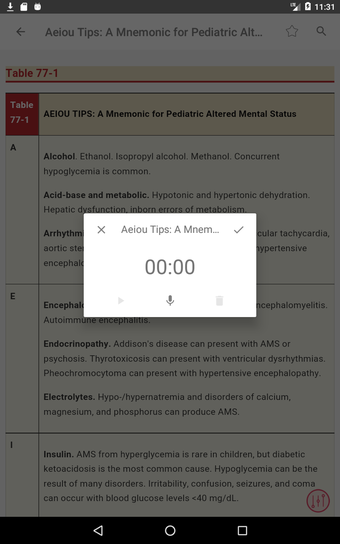

この無料アプリには、日常の実践に役立つ多くの情報が含まれています。このアプリでカバーされるトピックは、疾患から薬剤、さまざまなタイプの傷害まで幅広く、患者ケアを担当する人々にとって素晴らしいリソースです。